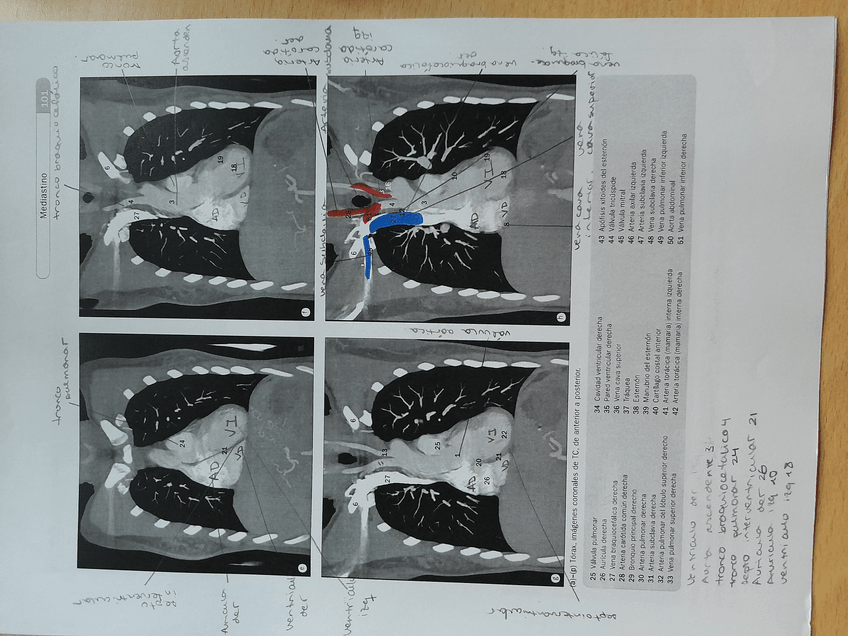

ANATOMIA

Columna, cintura, extremidades…